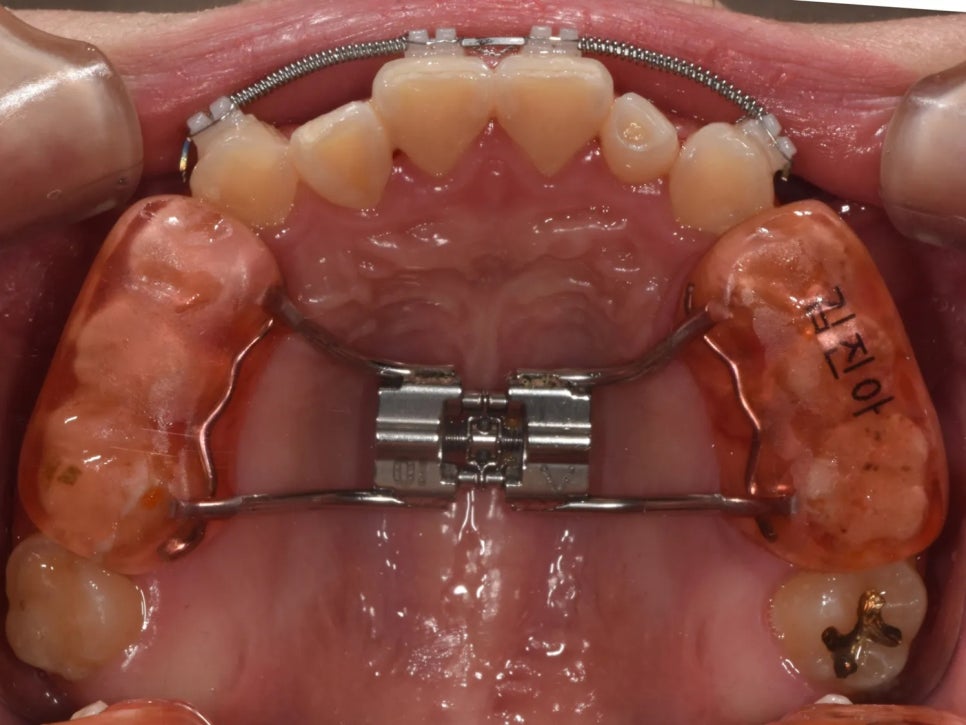

치료 1단계 – 위턱 확장 및 앞니 공간 확보

첫 번째 단계에서는 말씀드렸던 PBP를 적용했습니다. 이 장치는 입천장에 위치하면서 위턱의 치열을 양옆으로 넓혀주는 역할을 해요.

위턱을 넓히면서 동시에, 맨 앞니와 송곳니 사이의 공간을 벌려주었습니다. 이렇게 하면 안쪽으로 들어가 있던 두 번째 앞니가 제 위치로 나올 수 있는 공간이 생기게 되거든요.

여기서 재미있는 포인트가 있는데요, 송곳니 뒤쪽으로는 작은어금니, 큰어금니 같은 묵직한 치아들이 버티고 있기 때문에, 공간이 확보되면 앞니들이 자연스럽게 앞쪽(입술 방향)으로 이동하는 효과가 나타납니다. 이것이 바로 반대교합 해소의 첫 단추가 되는 거예요.

확장 장치(PBP)로 위턱을 넓히고, 두 번째 앞니의 배열 공간을 만들고 있는 모습